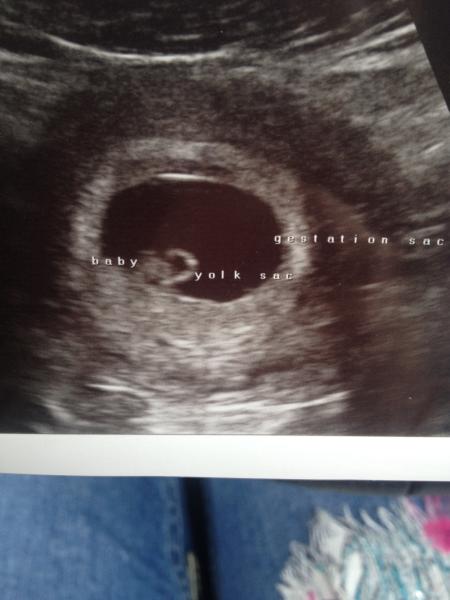

Eeeek just got back from early scan! She dated me as 6+4 which is about what I thought (give or take a couple of days!) Got to see the little heartbeat and even got a little DVD of it!! Will try as attached picture! (Not that you can see much it looks just like a blob!) haha

Lol! We keep calling it the little blob! Haha! Will have to think if a cuter nickname! It was lovely to see but as soon as we left I was saying I want to go again in a couple more weeks just to check on it! :-/ not sure my dp will agree to that though, might be a little too obsessive!!!

No they didn't fancy but it was more to my left side! She could only see one ovary actually but said it was because my stomach was grumbling with all the water id drunk so she couldn't get to the other one! Haha!

I was told my right and so I'm guessing that's why my blob was on the right and yours is left?

Lol! I'm not the only one calling it a blob then! :-)